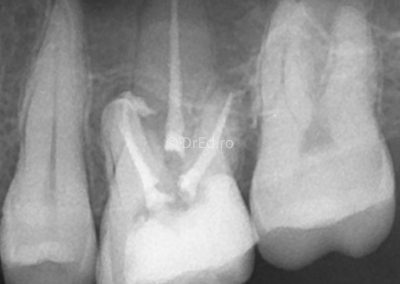

Galerie

Toate imaginile, fotografiile și radiografiile publicate pe acest site sunt protejate prin drepturi de autor și constituie proprietatea exclusivă a Dred.ro.

Aceste materiale sunt furnizate exclusiv în scop informativ și educațional și nu conțin date cu caracter personal sau informații care permit identificarea pacienților, în concordanță cu legislația privind protecția datelor cu caracter personal și GDPR.

Reproducerea, copierea, distribuirea, publicarea, transmiterea, modificarea sau orice altă utilizare, integrală ori parțială, a acestor materiale, în orice formă și prin orice mijloace, fără consimțământul prealabil scris al titularului drepturilor, este strict interzisă și poate atrage răspunderea civilă și/sau penală, în condițiile legii aplicabile privind drepturile de autor și protecția proprietății intelectuale.